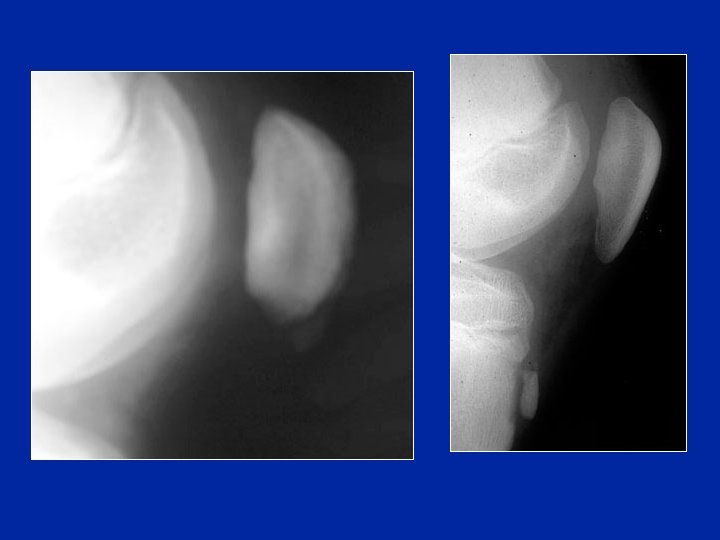

Aspects cliniques et radio • Symptomatologie proche de l’Osgood • Confusion possible avec un syndrome rotulien • Douleur précise à la pression de la pointe de la rotule. • Radiographie : petites modifications de la pointe de la rotule et parfois un petit fragment détaché

Séquelles Les séquelles sont rares, elles sont morphologiques modification de la forme de la pointe de la rotule qui parait parfois allongée : "rotule en goutte" Radios E Brunet-Guedj

Séquelle classique «the nose»

Ostéochondrose de la rotule Fragmentation de la rotule Guérison 1 an plus tard